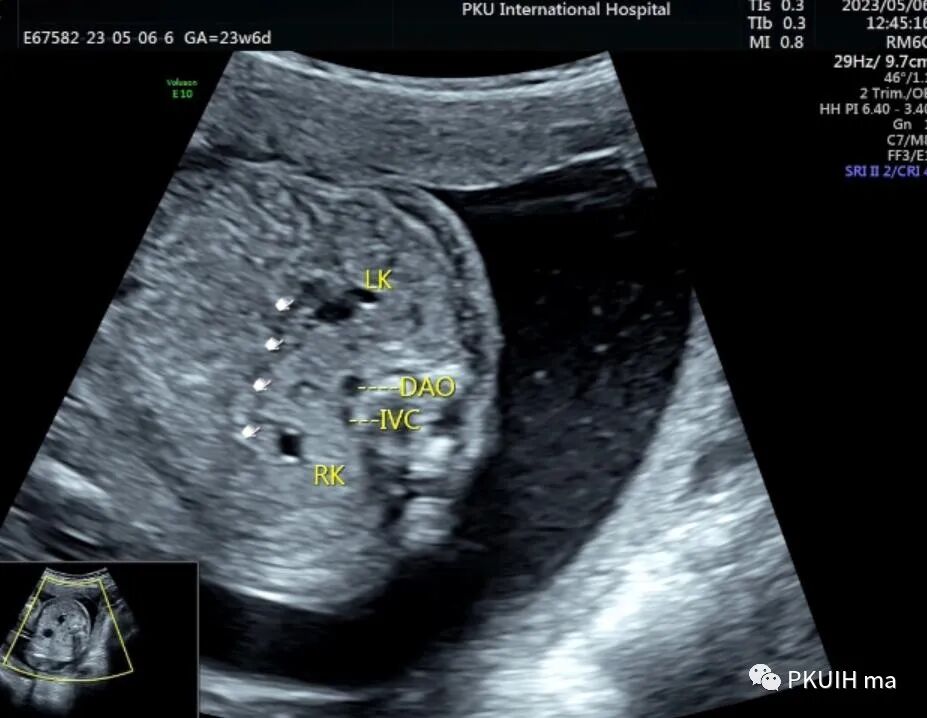

仔细观察双肾下极越过腹主动脉于腹主动脉和下腔静脉的前方相融合,同时肾的位置相对低,下极接近胎儿膀胱。(DAO:降主动脉,IVC:下腔静脉,BL:膀胱)